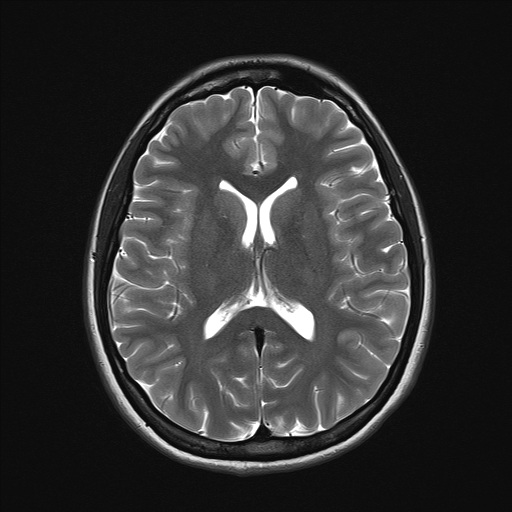

Serviço de segunda opinião e revisão técnica de exames de imagem em Neurorradiologia e Cabeça e Pescoço, com análise criteriosa de Tomografia Computadorizada (TC) e Ressonância Magnética (RM), fundamentada em critérios radiológicos atualizados e correlação clínico-radiológica.